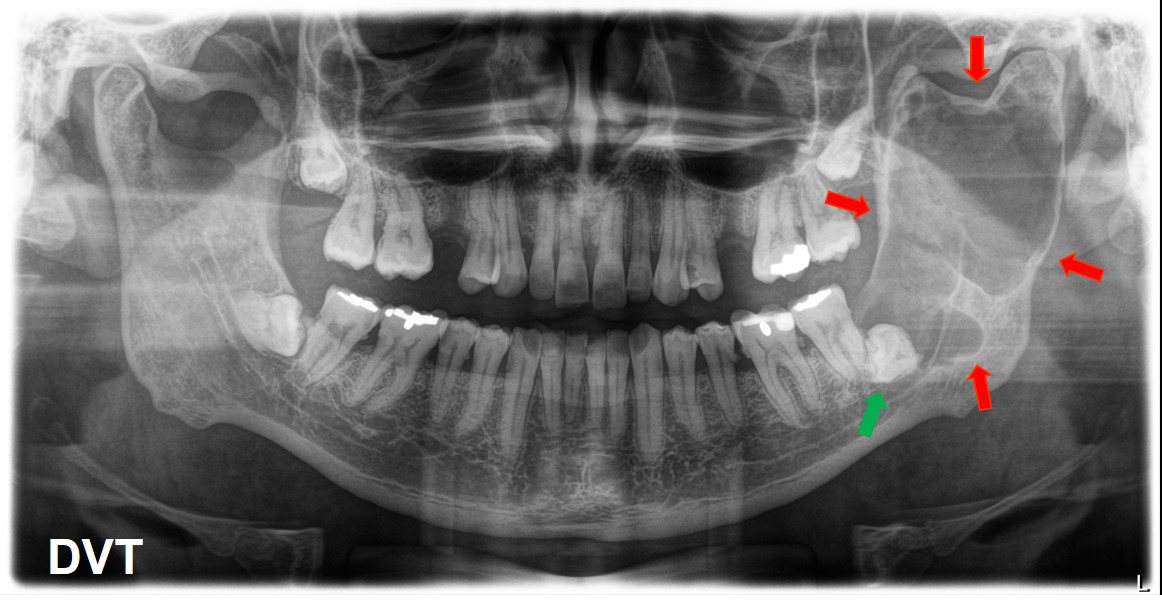

Digitale Volumentomographie

- Zystische Raumforderung im linken Kieferwinkel (rot)

- Assoziation mit retiniertem Zahn (grün)